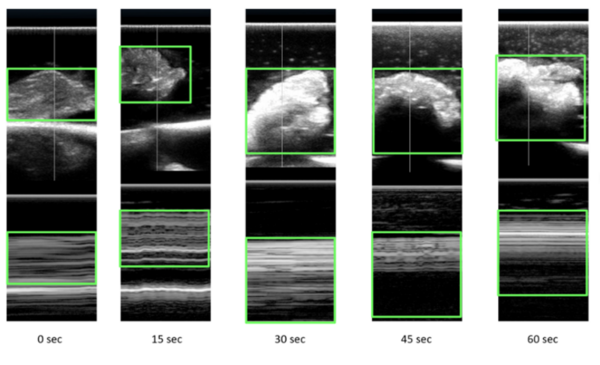

Microwave energy (ME) is used in the medical field to denature protein structures, resulting in inactivation or destruction of abnormal cells. Identifying the extent of destruction of abnormal tissue (cancer tissue or tissue with abnormal electrical activity) is essential for accomplishing successful therapy and reducing collateral damage. Our study was an ex vivo assessment of the changes on ultrasound scans (US) in chicken tissue exposed to ME. We hypothesized that any changes in tissue structures would be recognized on the reflected ultrasound waves. Ultrasound scans of tissues change with exposure to microwaves with increasing reflection of ultrasound waves. With exposure to microwaves, surface level brightness on the ultrasound scans increases statistically significantly. The findings could be used in heat related (ME and radiofrequency) procedures where clinicians would be able to actively assess lesions in real-time. Further studies are required to assess changes in tissue during active exposure to different types of energies.